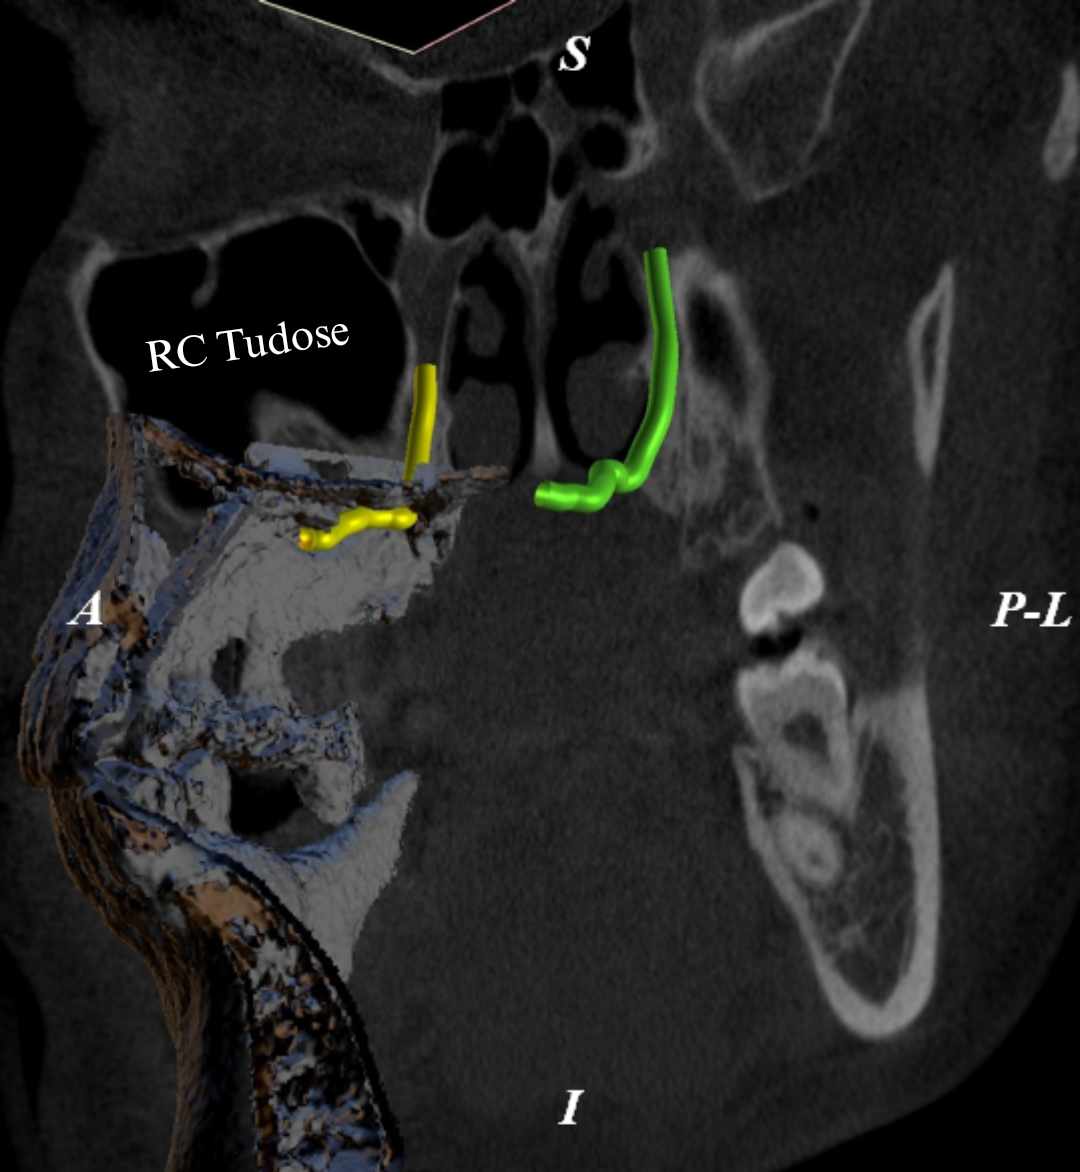

Oral Presentation - CBCT assessment of the greater palatine canal

Oral Presentation - The Zygomatic Implant: An anatomical view of the potential risks